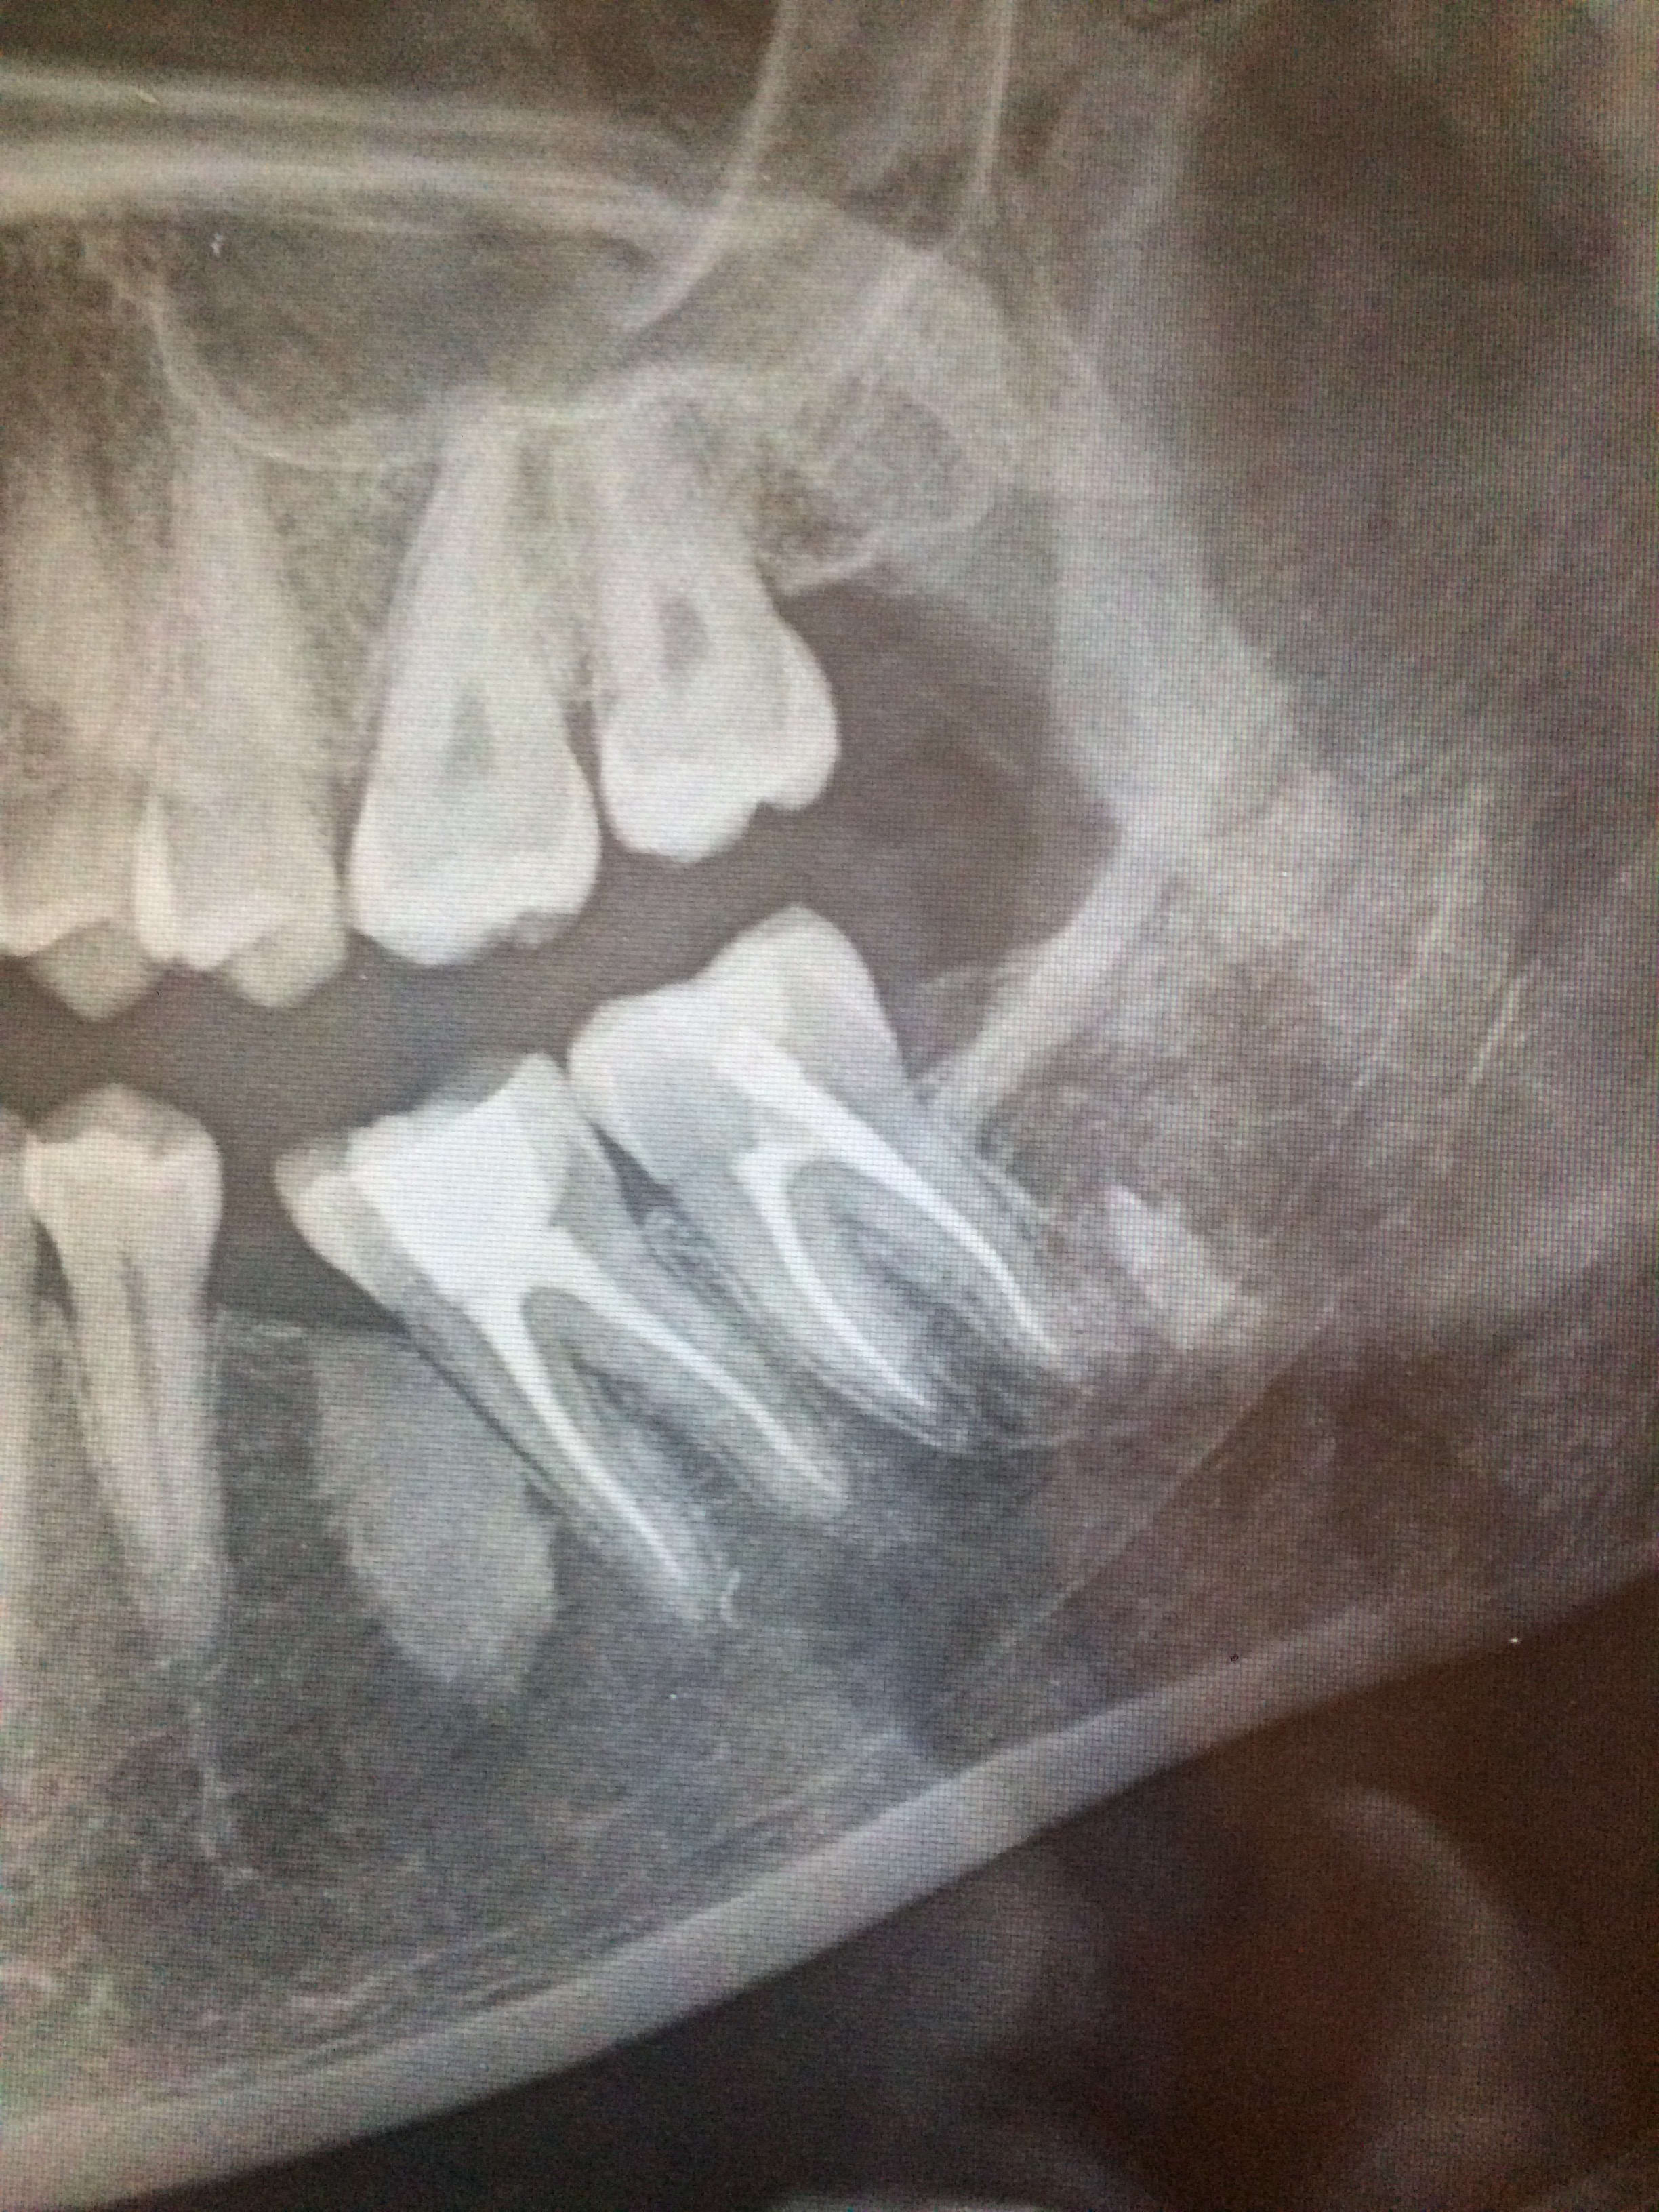

Auriez vous une idée sur l’image en M de 37 ?

Actuellement asymptomatique.

Codensation osseuse.....

Perso j'adresserai aà sto au cas où...